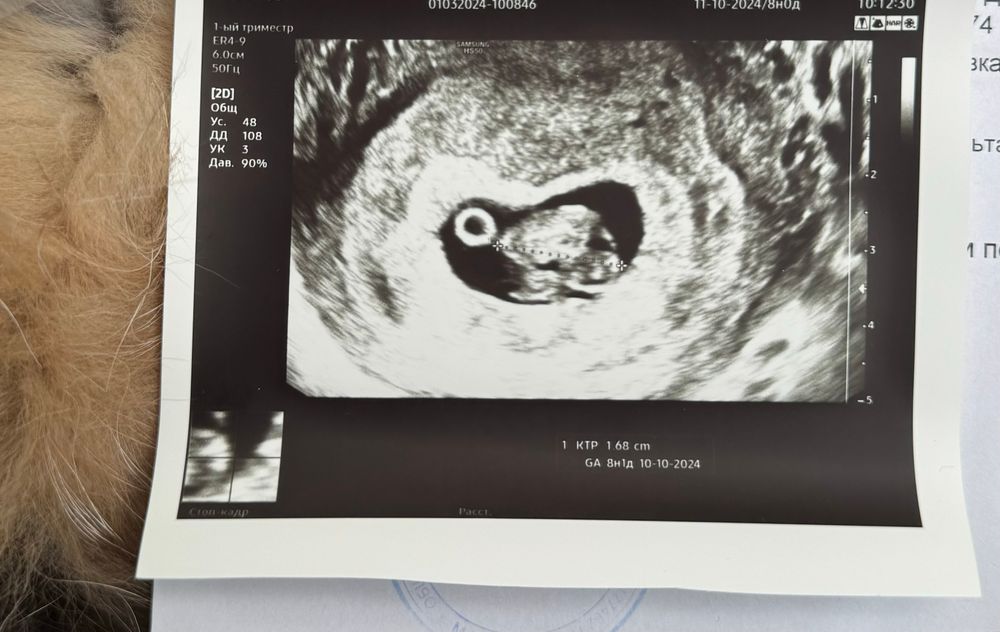

8 недель ровно ктр и пя

Ктр 1,6 мм, плодное яйцо 26 мм. Узист сказала , что все ок, пя отстает на 1 день, ктр идет в срок. Почему то выглядит так как будто эмбриону тесно. Кто сталкивался, чем закончилось